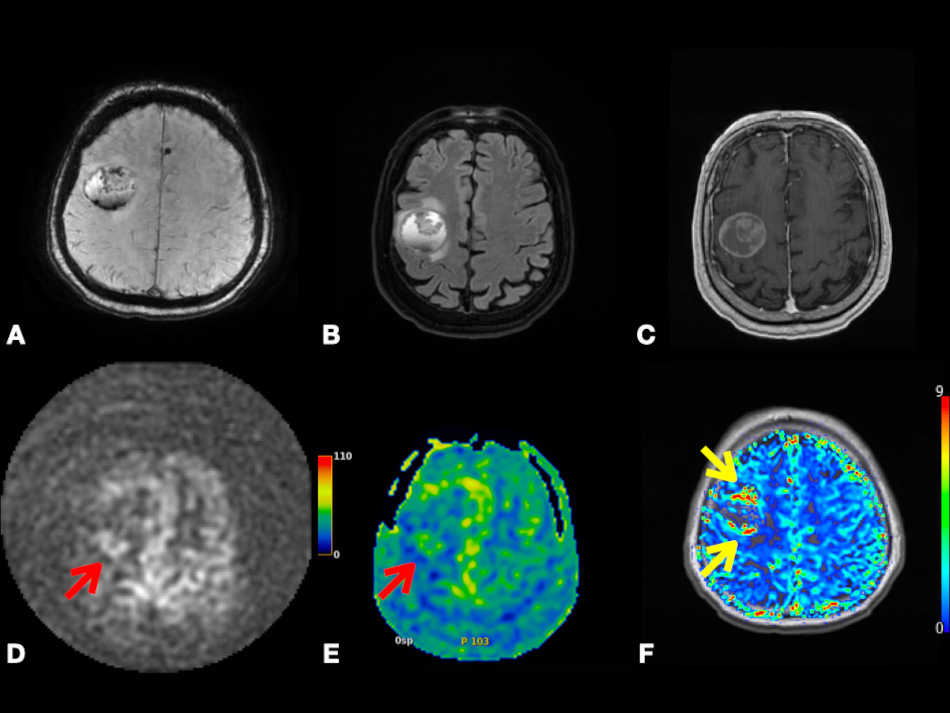

In contrast to conventional MRI, which delineates the anatomical structures and shows gross changes in the structure of the tumor, advanced MRI techniques represent dynamic physiological properties of tissue, which may be helpful in differentiating undiagnosed lesions based on properties including vascularity, cellularity, and metabolism [7, 8, 9]. The term advanced MRI techniques is used throughout this article to refer to dynamic contrast-enhanced (DCE) MRI, dynamic susceptibility contrast (DSC) MRI, diffusion-weighted imaging (DWI), arterial spin labeling (ASL) MRI, and blood oxygen level-dependent functional MRI (BOLD fMRI). In Figs. 1,2, we present different MRI images of two cases with different brain lesions including right frontal lobe oligodendroglioma (WHO grade II) and left lateral ventricle cavernous malformation. These two figures demonstrate the main differences between conventional MRI which delineates the anatomical borders of the brain lesions and advanced MRI techniques which demonstrate the internal physiologic features of different tumors, such as their vascularity, cellularity, perfusion, oxygenation, and microstructure.

Fig. 1.Right frontal lobe oligodendroglioma (WHO Grade 2). Axial ADC map (A), FLAIR (B), and post-contrast T1-weighted (C) images depicting non-enhancing tumor with T2 prolongation in gray and white matter and increased diffusivity (i.e., shine-through artifact). Axial pcASL source data (D), color-coded CBF map (E) from pcASL data, and color-coded rCBV map (F) from DSC data depicting no hyperperfusion. Abbreviation: ADC, Apparent diffusion coefficient; FLAIR, Fluid attenuated inversion recovery; pcASL, Pseudo-Continuous Arterial Spin Labeling; CBF, cerebral blood flow; rCBV, relative cerebral blood volume; DSC, Dynamic susceptibility contrast MR imaging.